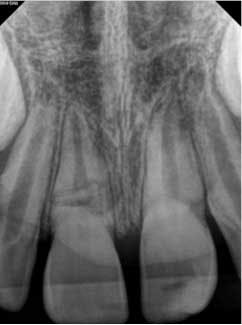

At approximately one year, the patient returned for follow-up. Clinical testing was equivalent to earlier recall visits. Radiographically, the tooth showed continued apical development with further development of a calcific barrier at the fracture line (figure 4). Furthermore, the medial aspect of the fractures showed repair.